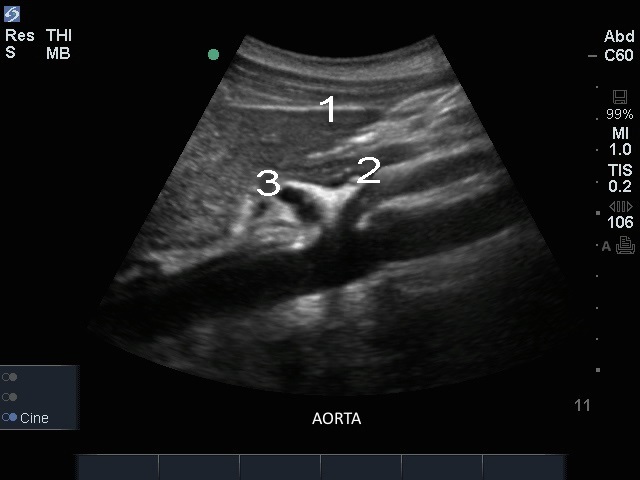

Edge: Aorta, sagittal

Leber

CA

Arteria mesenterica superior (AMS)